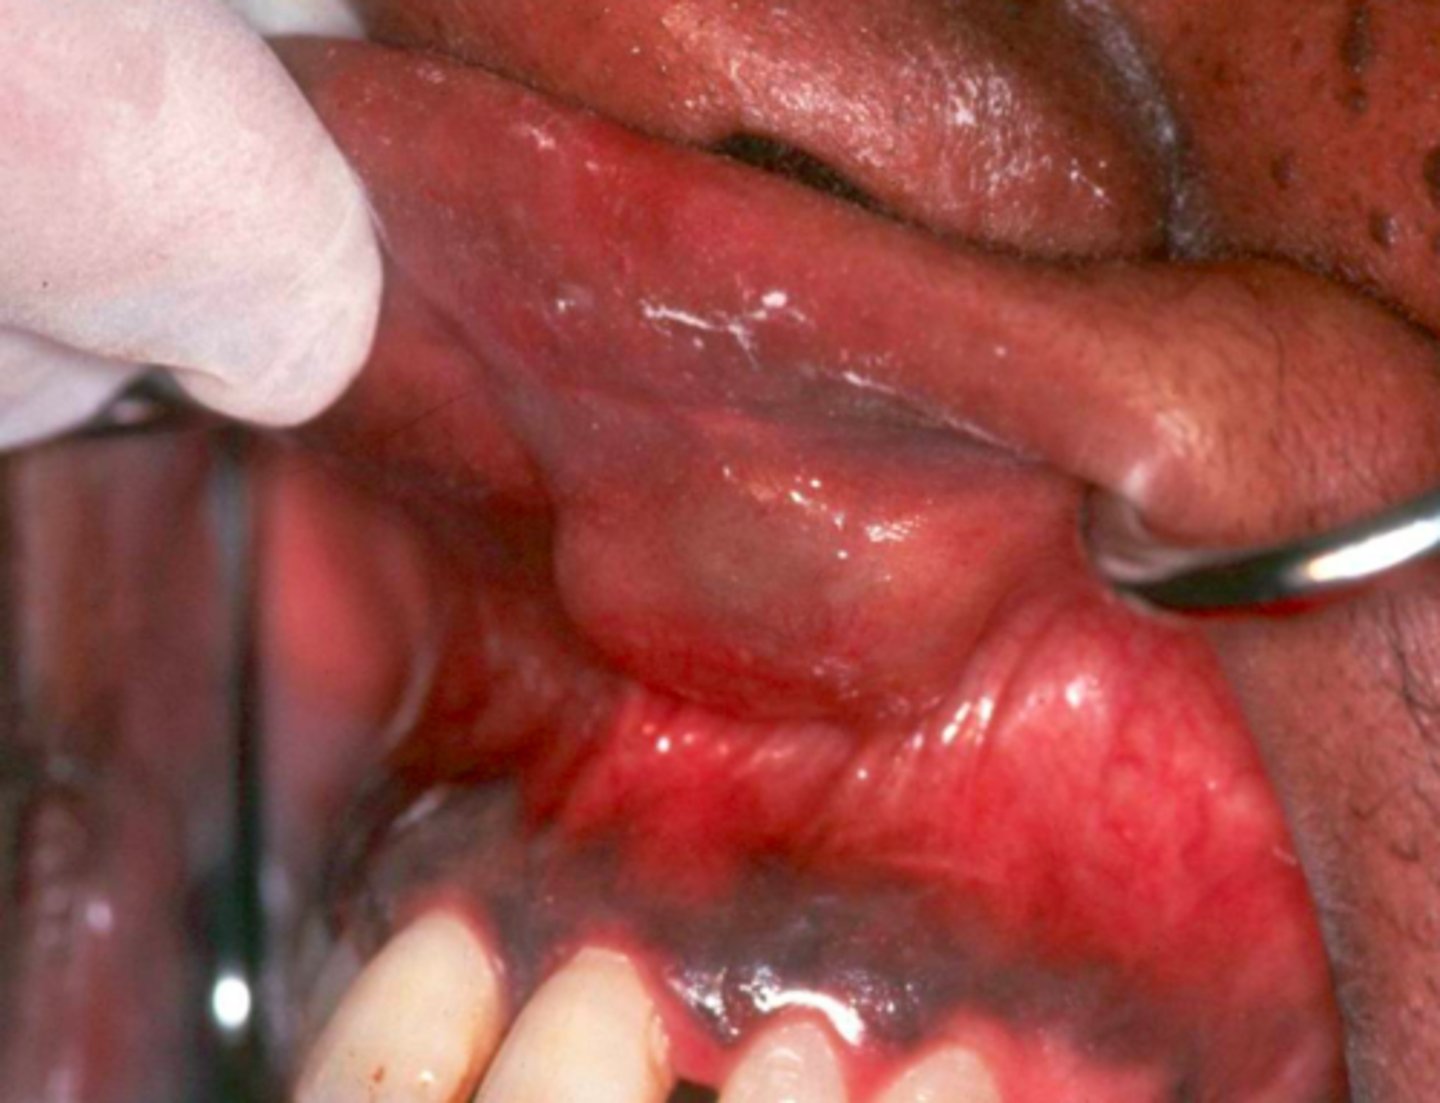

ID the pathology:

Mucocele

Ranula